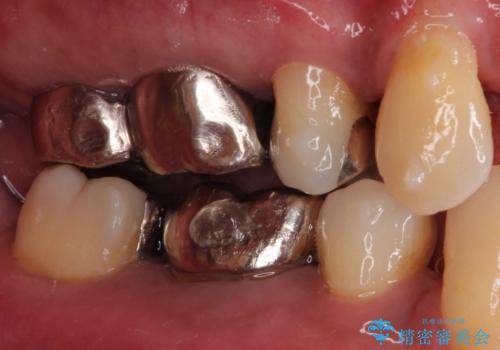

- 奥歯が痛いことを主訴に来院されました。

遠心根に歯根破折を認め、保存不可と判断しブリッジにて欠損補綴を行なっております。